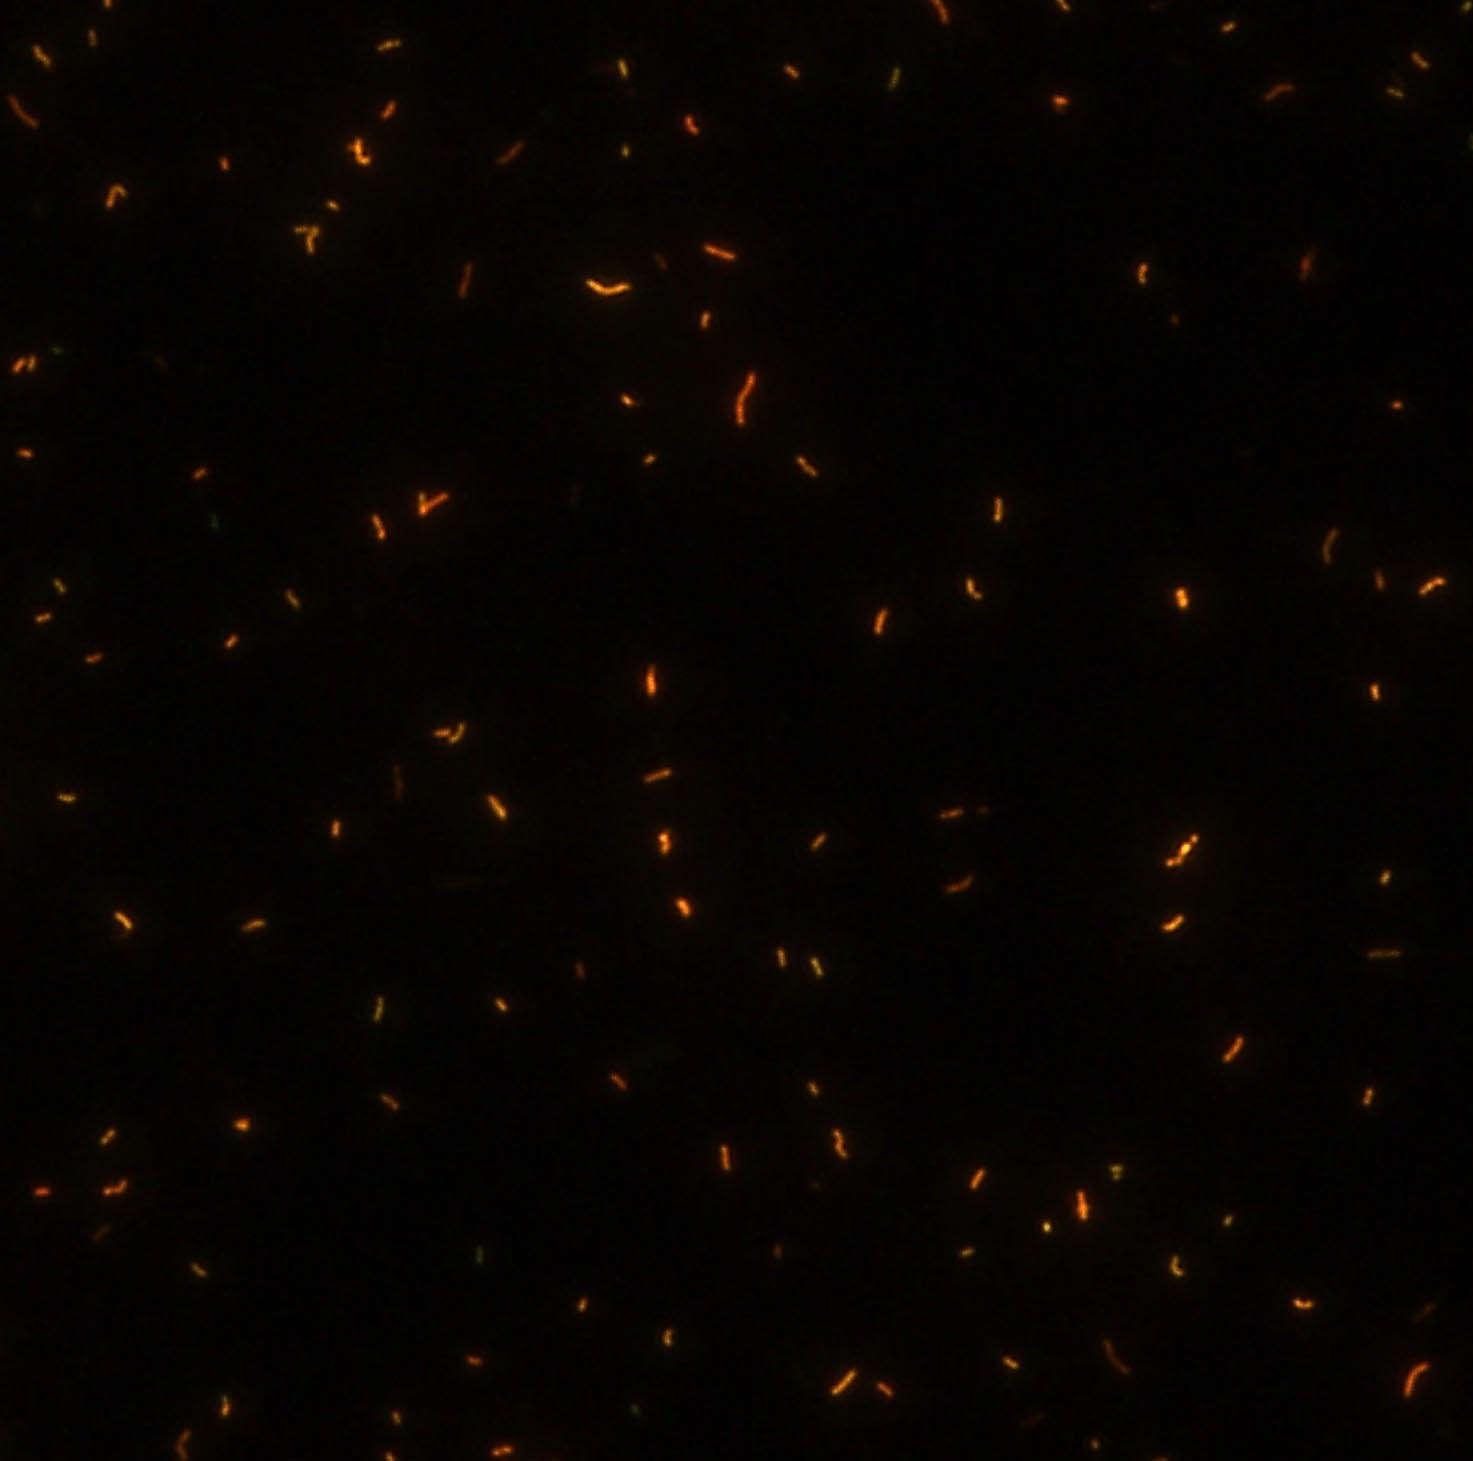

熒光法×400